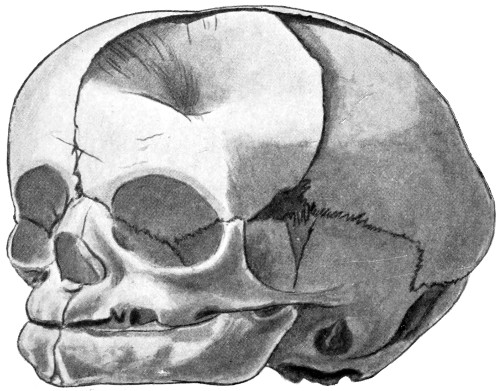

| 20. An occipital cephalocele | 33 |

| 22. An occipital cephalocele | 37 |

| 23. A depressed birth-fracture | 45 |

Fig. 20. An Occipital Cephalocele. (For further description, see text.)

1. Occipital cephaloceles—the commonest variety—occupy, anatomically, two positions (1) between the two lower segments of the occipital bone (inferior occipital cephaloceles), often involving the foramen magnum and sometimes complicated by a condition of cervical spina bifida, and (2) between the two upper segments of the occipital bone (superior occipital cephaloceles), occasionally involving the posterior fontanelle.

The tumour may possess a broad base or may be definitely pedunculated. In the former instance the gap in the bone may be of considerable size and the margins everted: in the latter case, the hole may be quite small.

The deformity is frequently associated with other congenital defects—hydrocephalus, microcephalus, spina bifida, hare lip, hernia, and talipes.

Fig. 21. A Cephalocele over the Anterior Fontanelle.

3. More rarely, the tumour overlies the anterior or posterior fontanelle. A case of this nature is depicted in Fig. 21, the tumour, situated over the anterior fontanelle, bulging over the temporal and frontal regions to a remarkable extent.

Sincipital cephaloceles are usually quite small, but the occipital variety and those situated in[35] the region of the anterior fontanelle frequently attain a great size (see Figs. 20-22).

Fig. 22. An Occipital Cephalocele. (For further description, see text.)